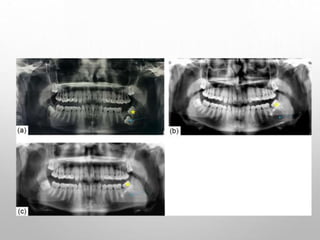

Year : 2017 | Volume : 29 | Issue : 1 | Page : 20-24

Predicting pathology in impacted mandibular third molars

Aveek Mukherji, Mohit Pal Singh, Prashant Nahar, Bhuvaneshwari S Balaji, Hemant Mathur, Saurabh Goel

Department of Oral Medicine and Radiology, Pacific Dental College and Hospital, Debari, Rajasthan, India

Asymptomatic patients who

decide to retain their third

molars should have periodic

clinical and radiographic

examinations to detect any

disease before it becomes

symptomatic.